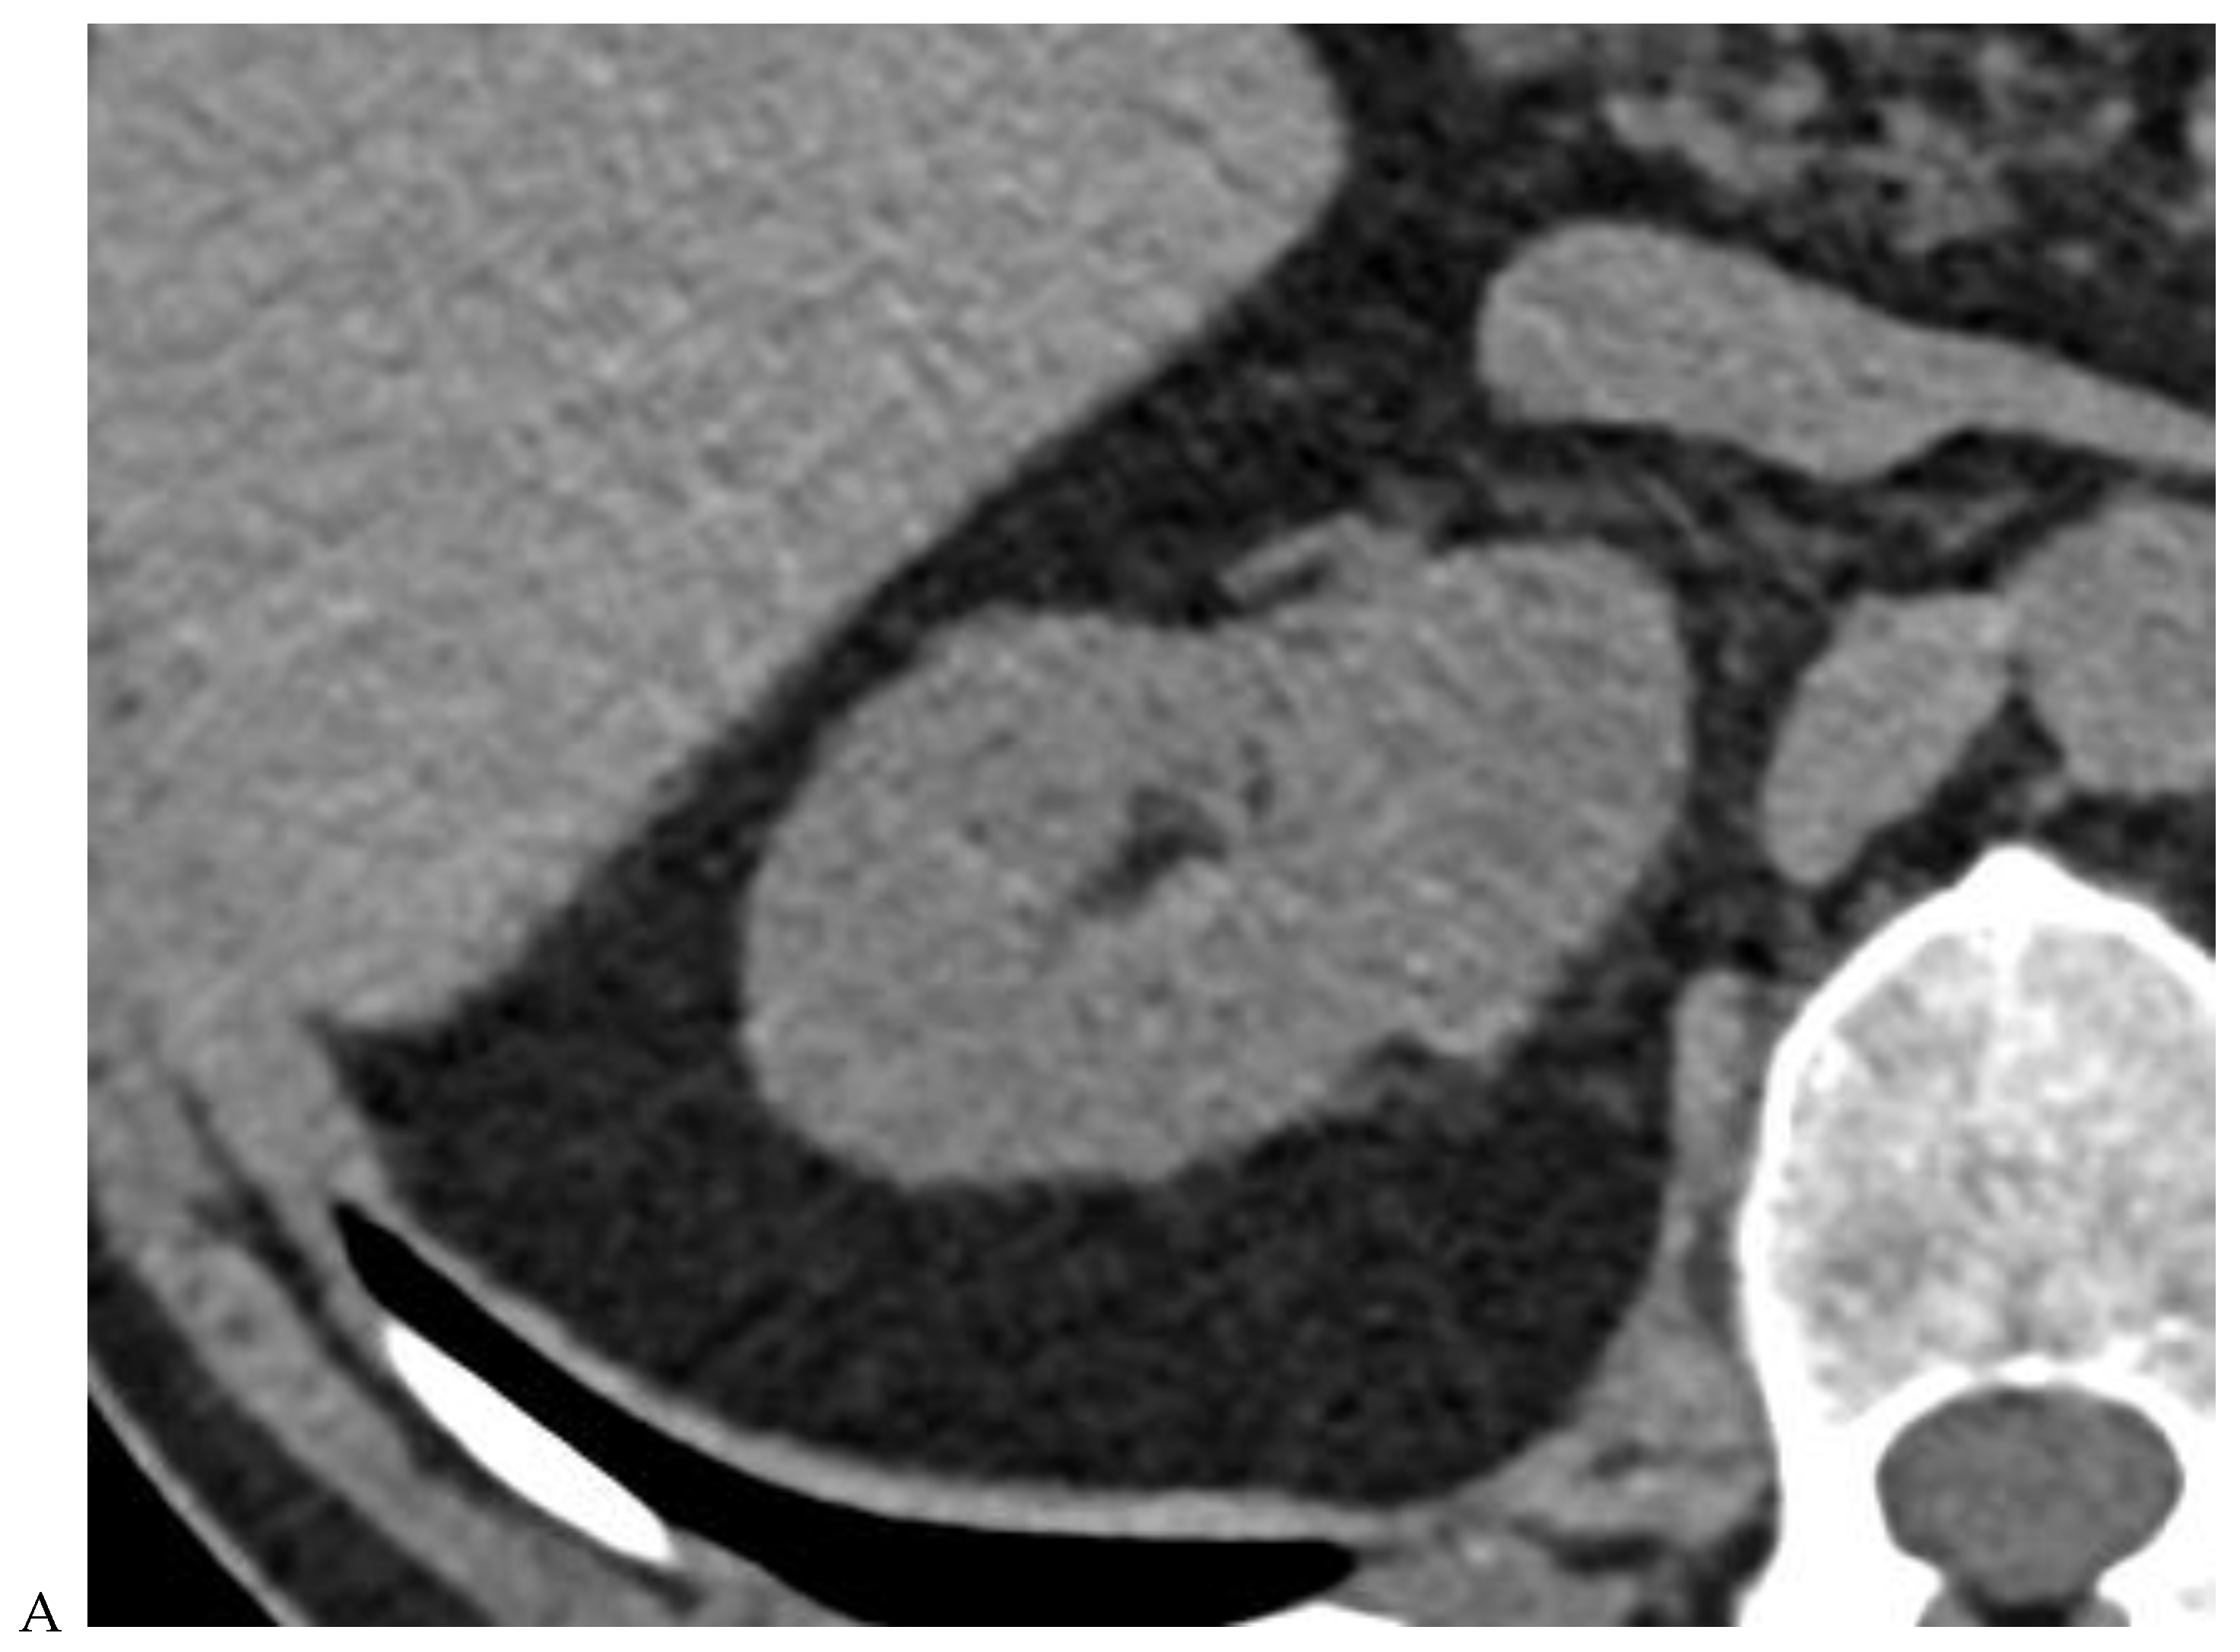

Figure 2.

Oncocytoma in the right kidney of a 42-year-old man. (A) On the unenhanced image, the 4.8 cm lesion is isodense relative to the renal parenchyma. Enhancement is seen on the corticomedullary phase image (B), followed by washout on the nephrographic (C) and excretory (D) phase images. (E) Macroscopic view of the lesion after radical nephrectomy. Courtesy of Pr S. Ferlicot, Department of Pathology, Bicêtre.